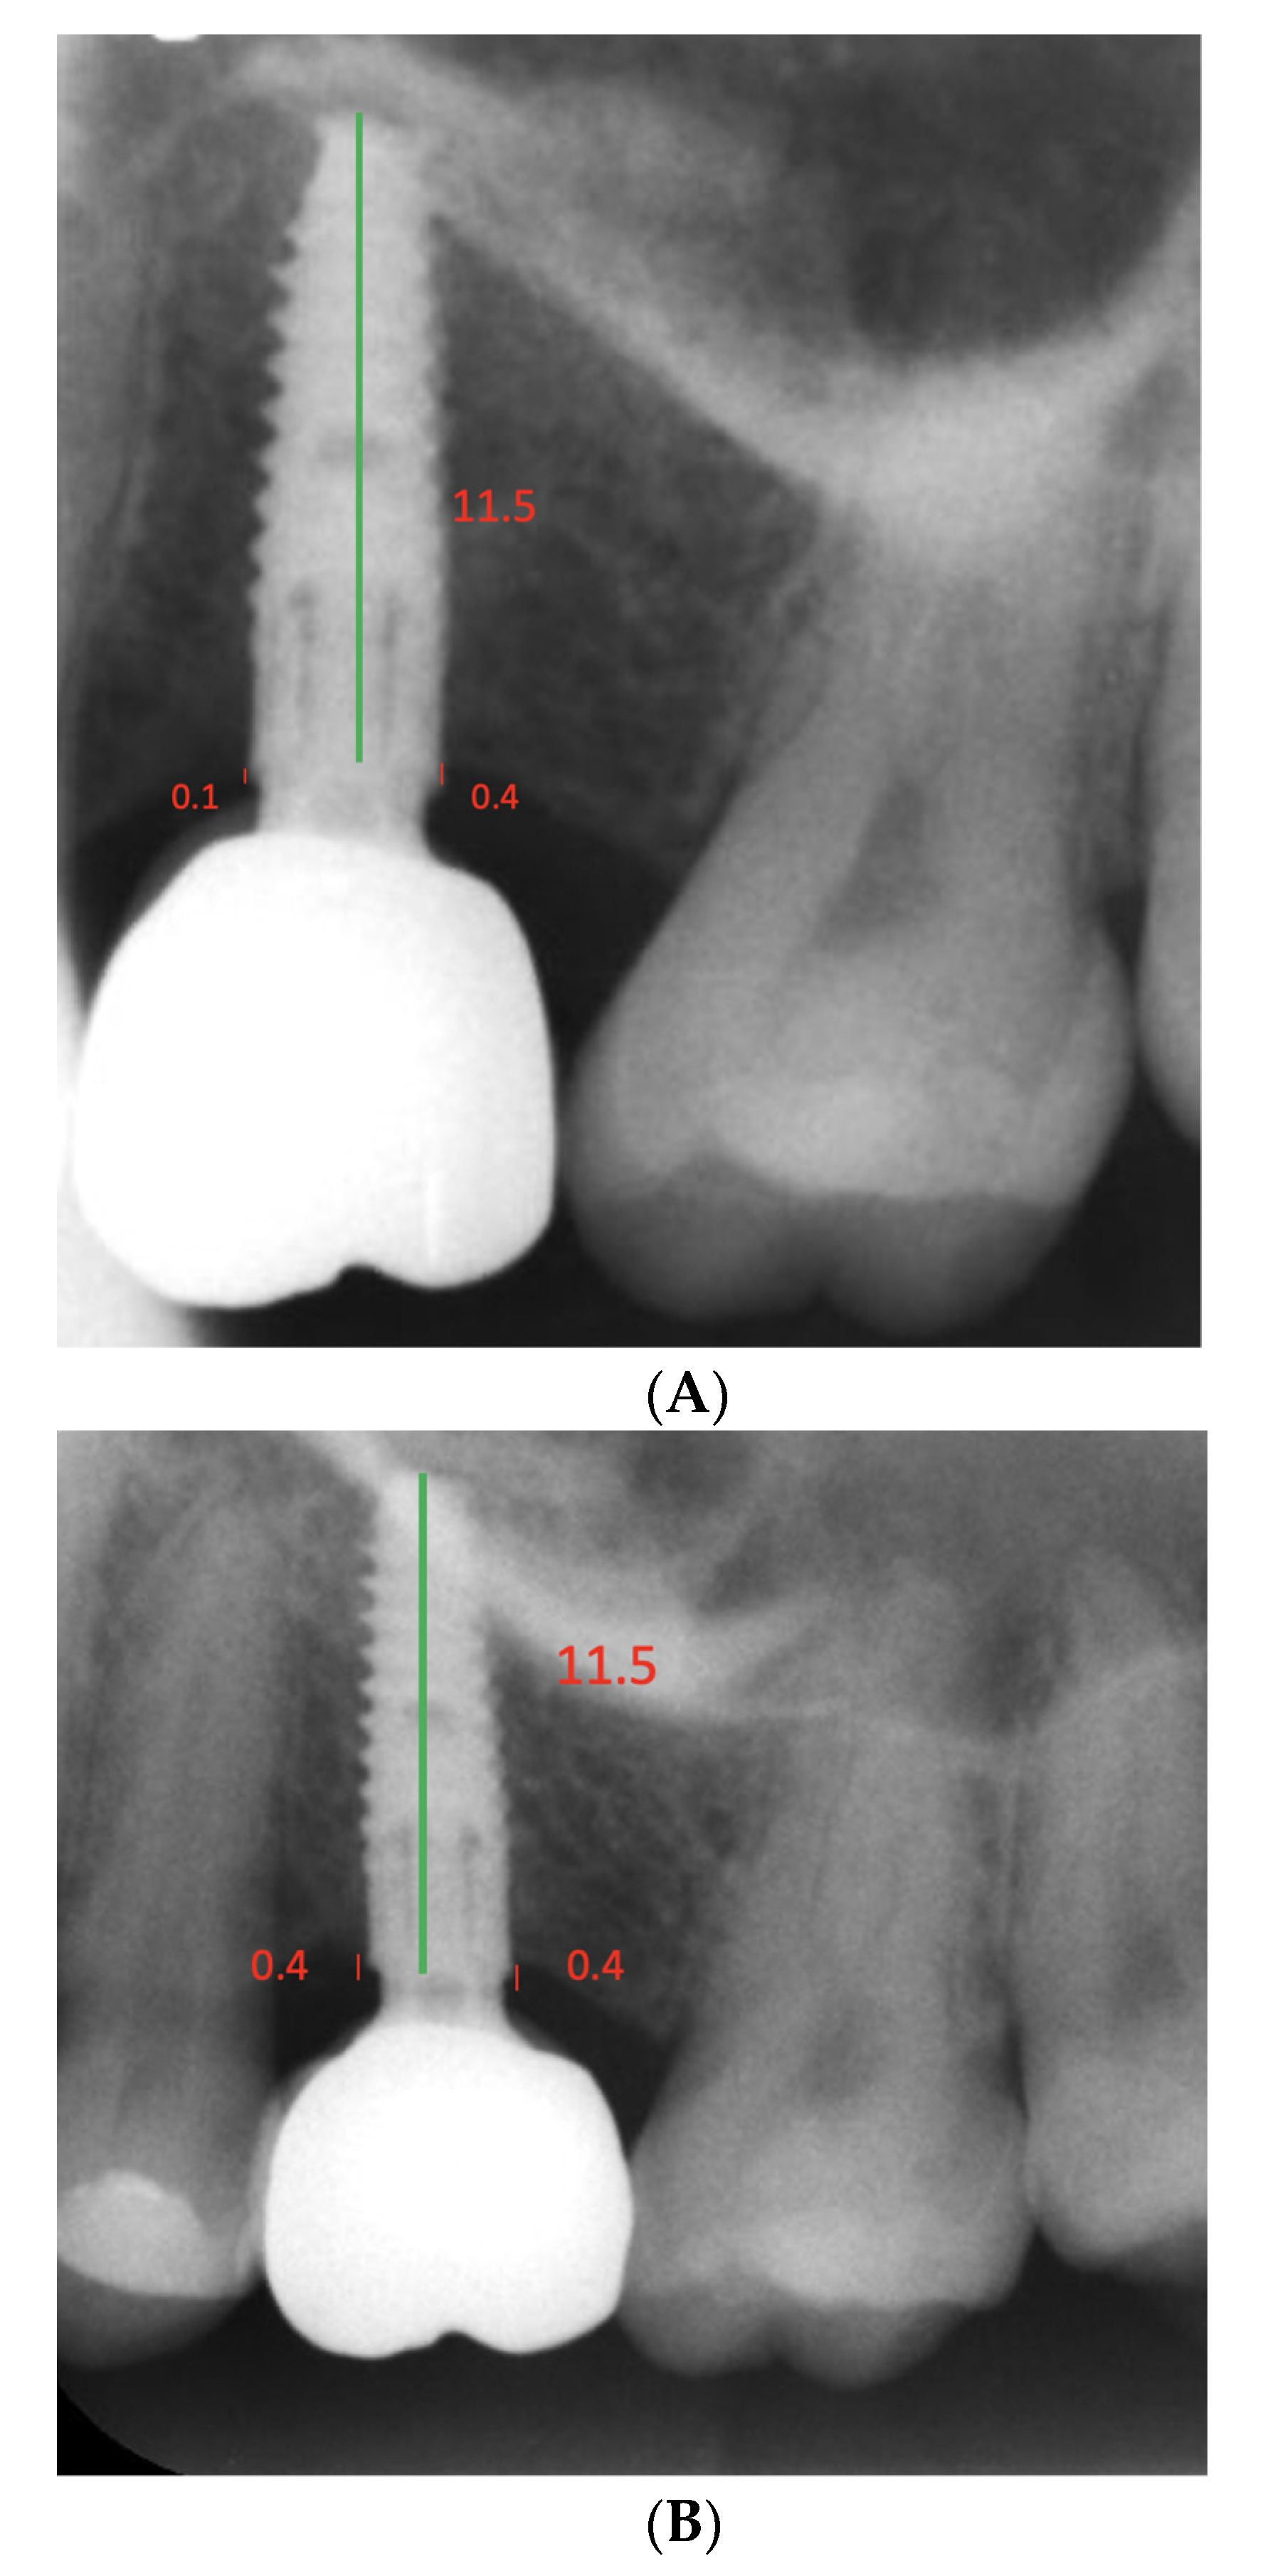

| 11.5 | 6 (24) | |||||

| 1 | 35 | F | 13 | Maxilla | 3.90 × 11.5 | 12 |

| 16 | 28 | M | 9 | Maxilla | 3.90 × 11.5 | 16 |